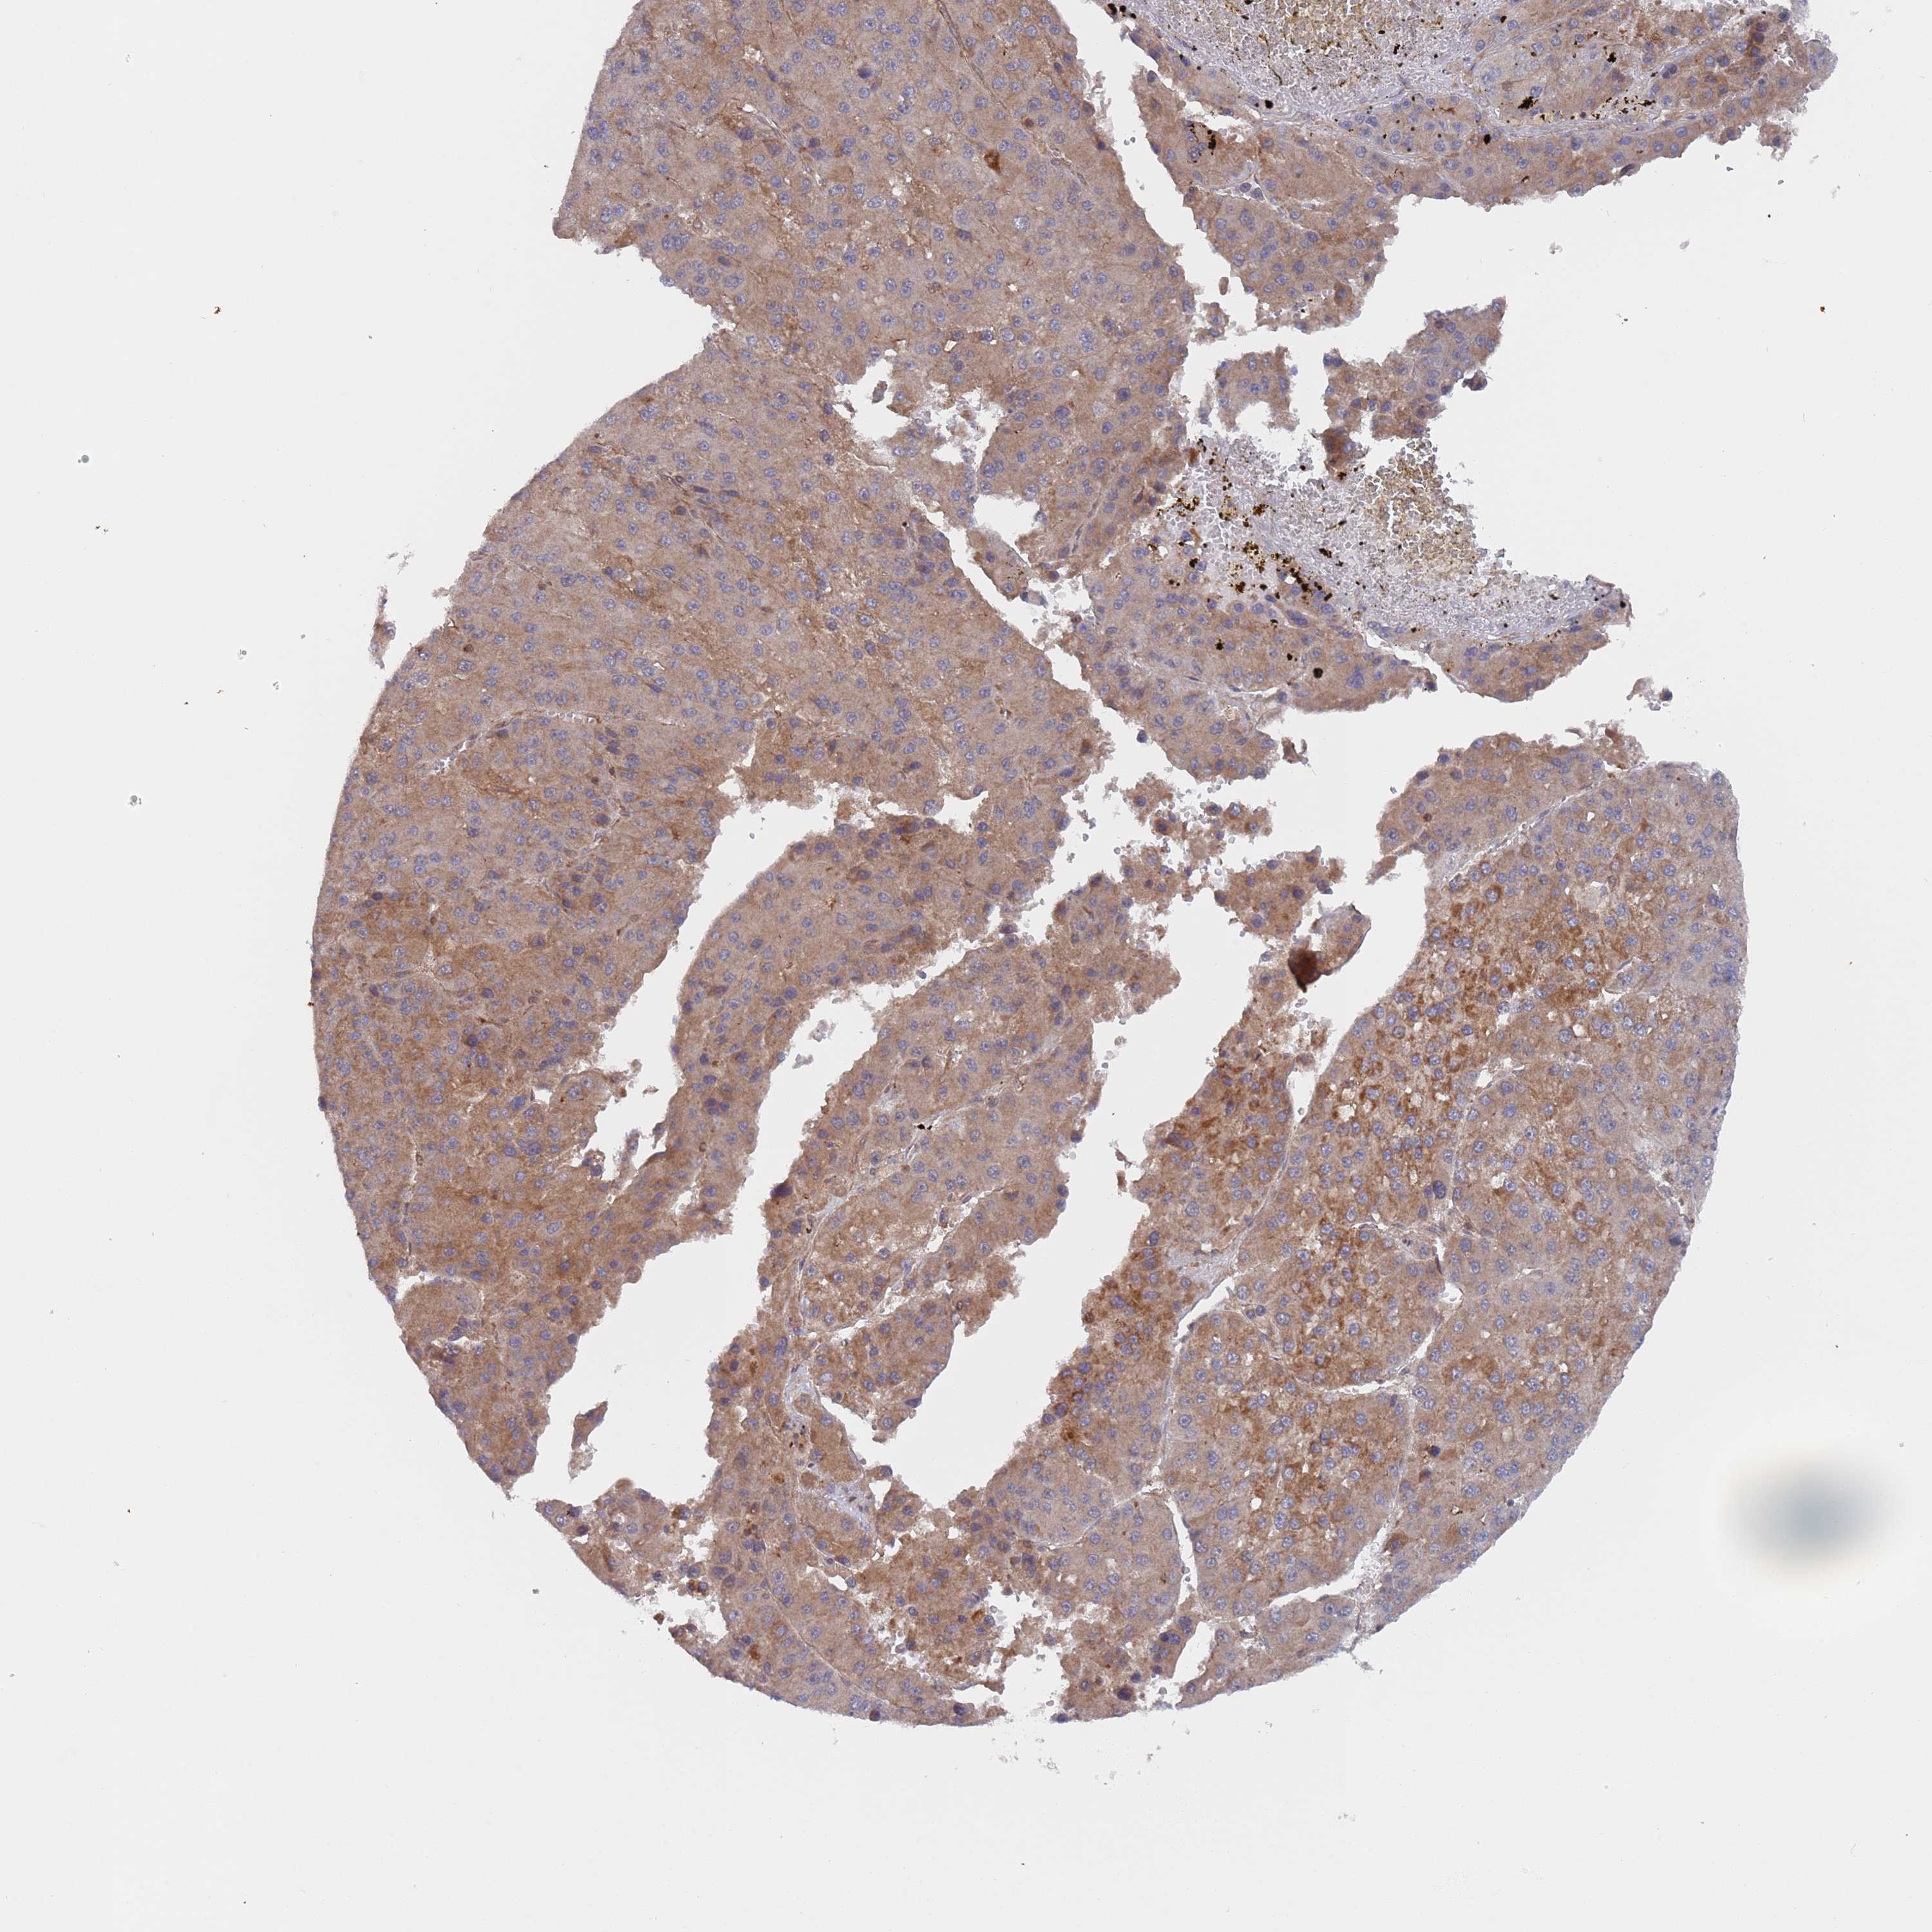

LIVER CANCER - Protein expressioni

A mouse-over function shows sample information and annotation data. Click on an image to view it in a full screen mode. Samples can be filtered based on level of antibody staining by selecting one or several of the following categories: high, medium, low and not detected. The assay and annotation is described here.

Note that samples used for immunohistochemistry by the Human Protein Atlas do not correspond to samples in the TCGA dataset.

Antibody stainingi

Antibody staining in the annotated cell types in the current human tissue is reported as not detected, low, medium, or high, based on conventional immunohistochemistry profiling in selected tissues. This score is based on the combination of the staining intensity and fraction of stained cells.

Each image is clickable and will lead to virtual microscopy that enables deeper exploration of all samples and also displays staining intensity scores, fraction scores and subcellular localization as well as patient and tissue information for each sample.

Antibody HPA046952

Staining

High

Medium

Low

Not detected

Intensity

Strong

Moderate

Weak

Negative

Quantity

>75%

75%-25%

<25%

None

Location

Nuclear

Cytoplasmic/membranous

Cytoplasmic/membranous,nuclear

Cholangiocarcinoma

Carcinoma, Hepatocellular, NOS